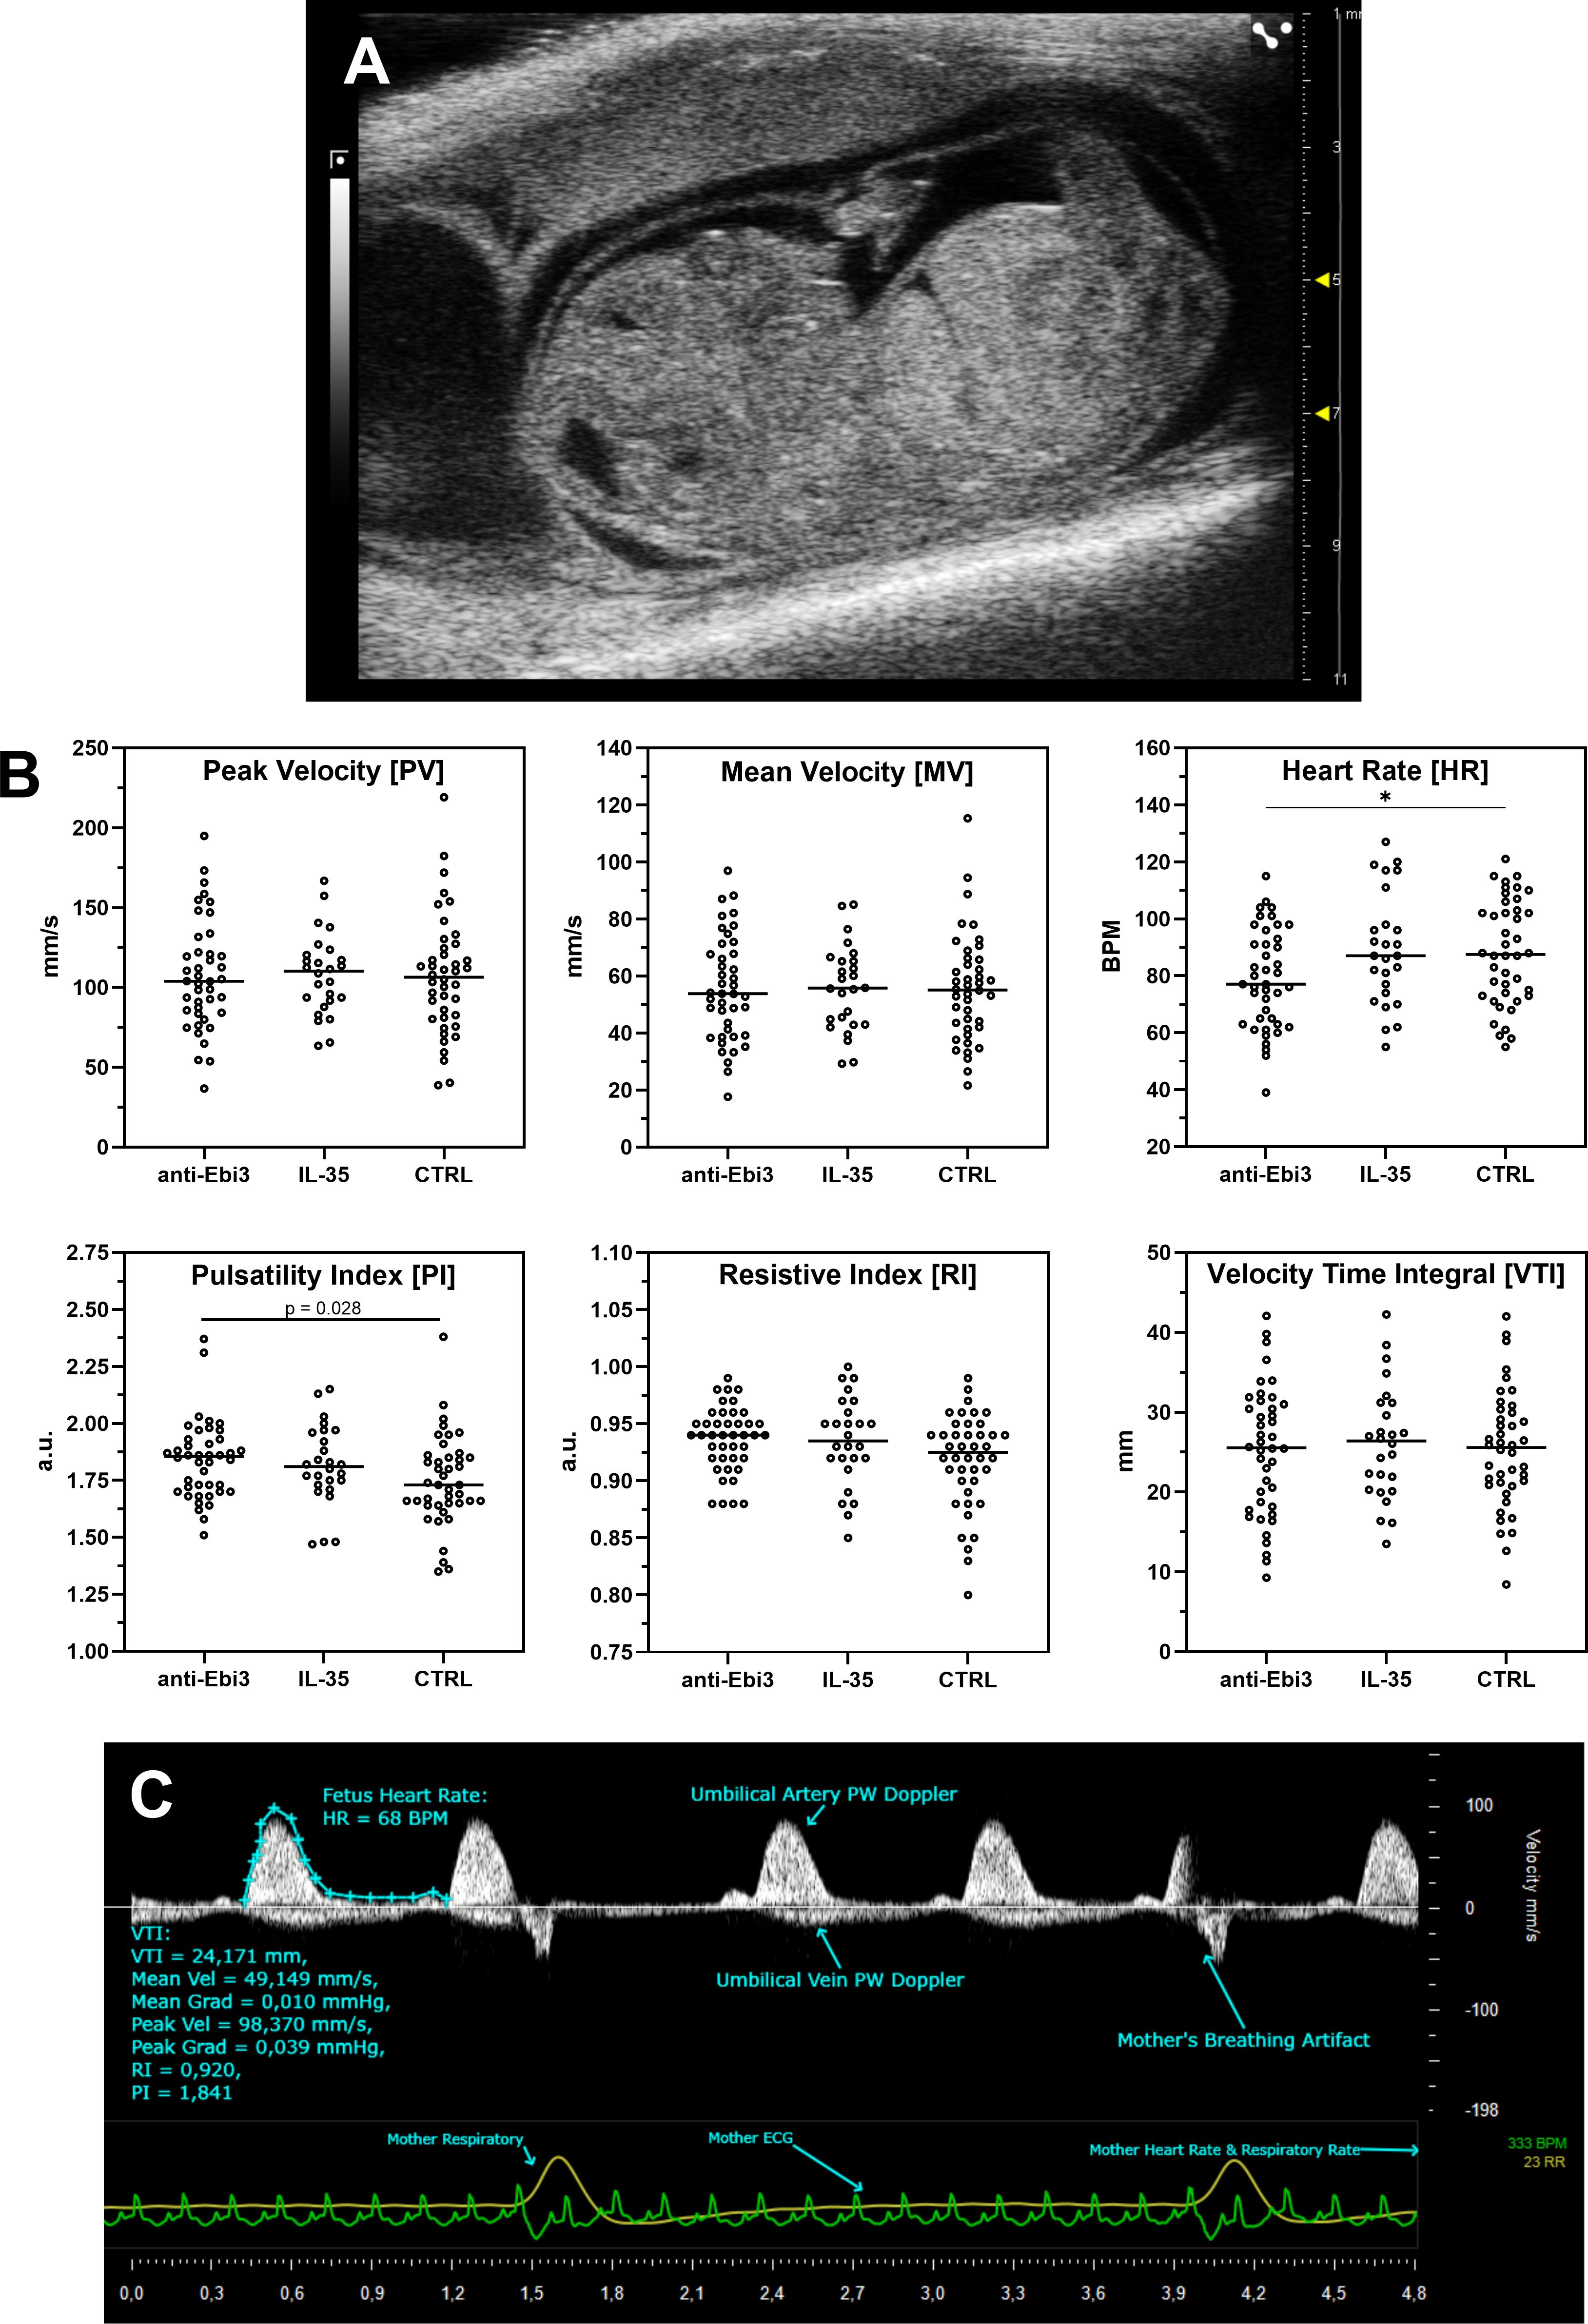

Figure 1A shows a representative picture of the uterus from abortion-prone mice with healthy and resorbed fetuses. Although in each examined group of animals we observed resorbed fetuses, we did not observe any differences in abortion rate between the examined groups (Figure 1B) after single dose administration of both rIL-35 and antibody anti-Ebi3. However, in the group that received the blocking antibody, ultrasound examination showed a significantly lower embryonic HR (Figure 2B) and lower circulatory competence of the fetal placenta, as indicated by an increased PI (Figure 2B) compared to the control group. Other parameters of ultrasound examination remained unchanged. IL-35 administration did not affect any of the parameters examined by ultrasound. Figure 2A shows a representative image of a murine fetus in the sagittal plane.

Ultrasound image of a fetus in panel A. Panel B shows scatter plot data on fetal blood flow parameters (Peak Velocity, Mean Velocity, Heart Rate, Pulsatility Index, Resistive Index, Velocity Time Integral) across three groups: anti-Ebi3, IL-35, CTRL. Panel C illustrates Doppler waveforms of umbilical artery and vein, highlighting maternal and fetal heart rates and respiratory artifacts.

Figure 2. Ultrasound analysis of umbilical cord blood flow following treatment. (A) Representative sagittal view of a murine fetus. (B) Quantification of key Doppler parameters. Each dot represents a measurement from an individual fetus, plotted to show the full data distribution. Crucially, all statistical analyses were performed using the dam as the experimental unit to account for the litter effect. Normally distributed parameters (Peak Velocity, Mean Velocity, Velocity Time Integral, Heart Rate) were analyzed with a linear mixed-effects model, while non-normally distributed parameters (Pulsatility Index, Resistive Index) were analyzed with a Kruskal-Wallis test on dam-level medians. Cetral line in each dataset rep[resents median; *p<0.05 indicates a significant difference from the control group, determined by Dunnett’s or Dunn’s post-hoc test, respectively. (C) Representative Pulse Wave (PW) Doppler image showing key measured parameters.

IL-35, as a strong pleiotropic cytokine, also exerts a systemic influence. IL-35 targets not only conventional/effector T cells, Treg cells, and Breg cells, but also non-immune cells, including aortic endothelial cells (60). Therefore, we examined the cytokine profile in blood sera and umbilical blood flow in 14-day fetuses. We observed a significantly lower embryonic HR and less-developed umbilical vessels after anti-Ebi3 administration. The PI, a noninvasive and easy method for obtaining parameters with a broad range of research and clinical applications, was higher in this group than in the control group. It is generally believed that the PI of Doppler recordings in the umbilical arteries is a marker of the circulatory competence of the fetal placenta (61). In human pregnancy, high PI values of the umbilical artery correlate with fetal growth restriction markers and an increased risk of moderate and severe small-for-gestational-age at birth (62). In mid-gestation (10.5 dpc), an increased PI and resistance of the uterine arteries were observed in a mouse model of Treg deficiency, suggesting profound vessel impairment. Moreover, Treg depletion reduced Ebi3, p35, IL-10, and TGFβ mRNA expression. In contrast, IFNγ mRNA expression remains unchanged, whereas Vegfa expression was reduced than in the control mice. Ncr1, which encodes the uNK cell maturation marker NKp46, was also reduced in this study, which is consistent with the histological finding of fewer uNK cells in decidual tissues. The authors concluded that Treg cells (and particularly IL-35, a cytokine unique to Tregs) influenced NK cell frequency and possibly influenced placental vessel development (63). Our results confirmed that the restriction of IL-35 availability after anti-Ebi3 antibody administration may affect placental impedance to blood flow. However, compared to control mice, we observed that the frequency of decidual Tregs (CD45+CD3+CD4+Foxp3+), but not Tregs, expressing IL-35 (CD45+CD3+CD4+Foxp3+IL-35+) (data not shown, no difference between examined groups) increased after delivering this antibody. It can also be assumed that the antibody used neutralizes IL-35 originating from other sources, such as the trophoblast itself, or eliminates its protective effects within the vessels (16, 64). In addition, the frequency of IL-35-producing decidual NK and B cells increased after rIL-35 administration. These results may indirectly indicate the cooperation of these cells and the positive effect of IL-35 on the circulatory competence of the fetal placenta.